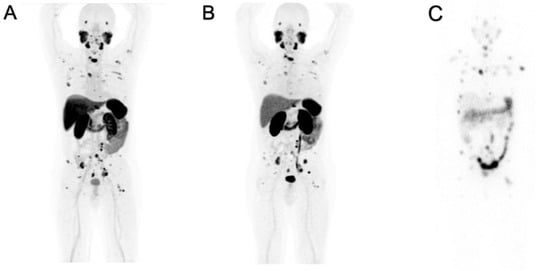

Nevertheless, the detection of PCa deposits, in our experience, was not significantly affected by the behavior of the two radioligands in normal organs/tissues. In the wide majority of cases, both radioligands depicted the same lesions with different levels of uptake as shown in Figure 1. This patient had an initial PET/CT exam with [18F]PSMA-1007, performed before RLT with [177Lu]Lu-PSMA-617, and the radioligand was concentrated within skeletal and lymph nodal metastases. After the first two cycles of RLT, the patient was reevaluated by PET/CT with [68Ga]Ga-PSMA-11, that documented the same lesions although with different uptake.

PET/CT images of both radioligands were also compared with planar, whole-body SPECT/CT images, acquired for dosimetric purposes 96 h after the first cycle (7.4 GBq of [177Lu]Lu-PSMA-617). All of the known lesions were seen by the three different PSMA-radioligands. Such a finding indicates that the selection of candidates for RLT may be reliable, independently from the used PET-PSMA radioligand.

Our experience also shows that among the different PSMA radioligands used to image or to treat PCa, there are no significant differences in their binding within tumor lesions. As shown in Figure 1, no differences in the biodistribution in lesions were identified among patients, which has been studied before starting RLT with [177Lu]Lu-PSMA-617 and imaged, after two cycles of RLT, with [68Ga]Ga-PSMA-11. The relevant aspect is the similar distribution and levels of uptake within malignant deposits among diagnostic ligands and therapeutic companions while some differences were observed in normal organs, mainly related to greater lipophilicity of [18F]PSMA-1007 vs. other radioligands.

Figure 1. Positive PET/CT scans performed with (A) [18F]PSMA-1007 (70–90 min p.i.) and with (B) [68Ga]Ga-PSMA-11 (45–60 min p.i.) for the same patient. Planar images (C) acquired with SPECT/CT γ-camera 96 h after administration of [177Lu]Lu-PSMA-617.